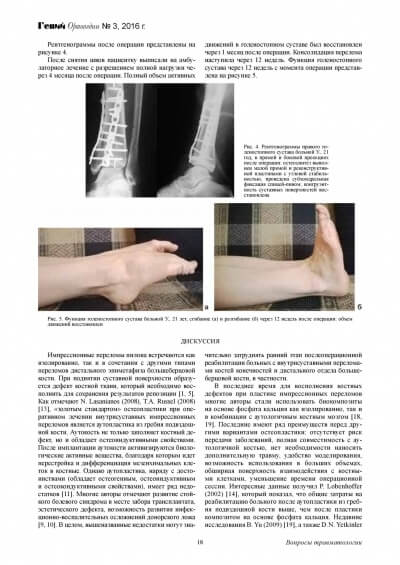

Определяем дизайн лоскута Рис.1